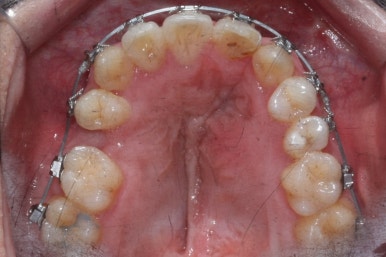

악궁확장이 시작될 시점과 악궁확장을 다 진행했을 시점의 비교입니다.

확실히 좁아져 있던 가로 넓이가 넓어진 것을 볼 수 있습니다.

악궁확장장치는 바로 제거할 경우 다시 원상태로 폭이 좁아질 수 있으므로 3~6개월은 유지해야 합니다.

치료 전과 가장 최근의 사진을 비교해 보겠습니다.

좌측이 부산구순구개열 전, 우측이 가장 최근의 사진들입니다.

거꾸로 물리던 앞니가 개선되었습니다.

좁아져 있고 찌그러진 위턱뼈의 형태가 개선되었습니다.

영구치 개수가 모자라는 선천결손이 있었지만 아랫니도 개수를 맞춰줌으로써 치아의 맞물림도 상당히 좋아졌습니다.